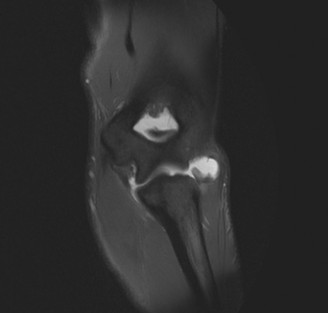

Identify the muscles that compose the force couples in the transverse and coronal planes? CASE 3 A 35-year-old male has had left shoulder pain for 4 months, ever since a low-speed motor vehicle accident (MVA). Physical examination demonstrates preserved range of motion but pain and some weakness with Jobe’s testing. His imaging is shown in Figure 2–8.

Figure 2–8_Reproduced with permission from Stadnick ME. _Partial Rotator Cuff Tears. MRI Web Clinic. 2007 (Apr).

What is the most likely diagnosis?

The correct answer is (A). These are best diagnosed on an MRI as seen in the imaging provided; addition of intra-articular contrast can further improve this study. Answer B, full-thickness rotator cuff tear, is incorrect as the bursal side of the tendon can be seen to be in continuity. Answer C, a SLAP lesion, will be visualized as a labral tear on a coronal MRI and will be found at the biceps root. Answer D, an ALPSA lesion, will be most clearly seen on an axial MRI. It is a variant of a Bankart lesion where the labrum is displaced medially and inferiorly rolling down the glenoid neck underneath the periosteum.

MRI remains the most popular imaging modality for diagnosing rotator cuff tears. Normal rotator cuff tendon appears dark on both T1 and T2 sequences. Tears may be noted as being full-thickness, articular-sided, bursal-sided, or intrasubstance. They are visualized as a disruption in the regular contour of the tendon and increased signal intensity on T2 sequences. Occasionally, an MR arthrogram may provide additional information regarding a cuff tear, although this is not routinely ordered.